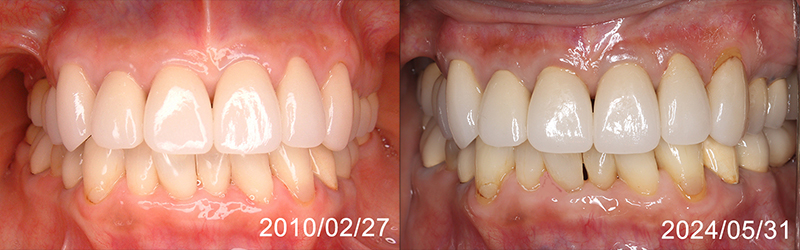

現在80歳を超えた方々が60歳半ば以降70歳代半ばころまでに、ご自身の歯を思い切ってオーバーホールした後の10年以上の経過を供覧いたします。

60代半ばでの前歯の再修復

82歳で17年間再修復が維持されています

70代半ばでの前歯の再修復

前歯が外れ始めて再治療をして12年経過